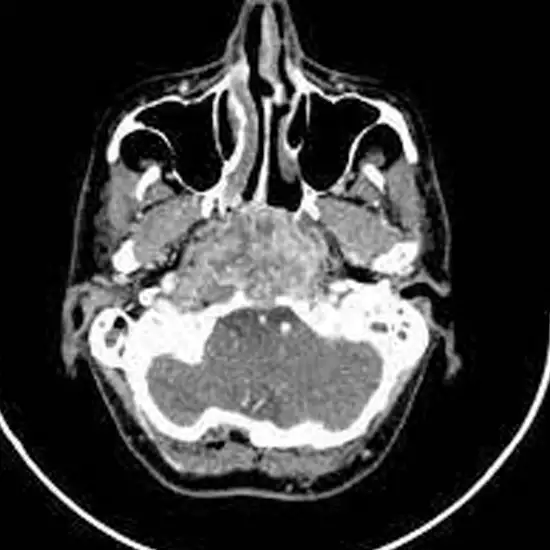

CECT (Contrast Enhanced Computed Tomography) Nasopharynx is an imaging scan used to view the cross-sectional images of the nasopharynx, air-filled hollow sinuses, and pharynx. It helps in identifying and assessing the inflammation of the pharynx, inflammation of the larynx, sore throat and nasal obstruction.

CECT (Contrast-enhanced Computed Tomography) screening of the nasopharynx is a non-invasive radiology test used to evaluate the nasopharynx and surrounding tissue. CECT Nasopharynx is done to look for the conditions of the nasopharynx and the surrounding area.